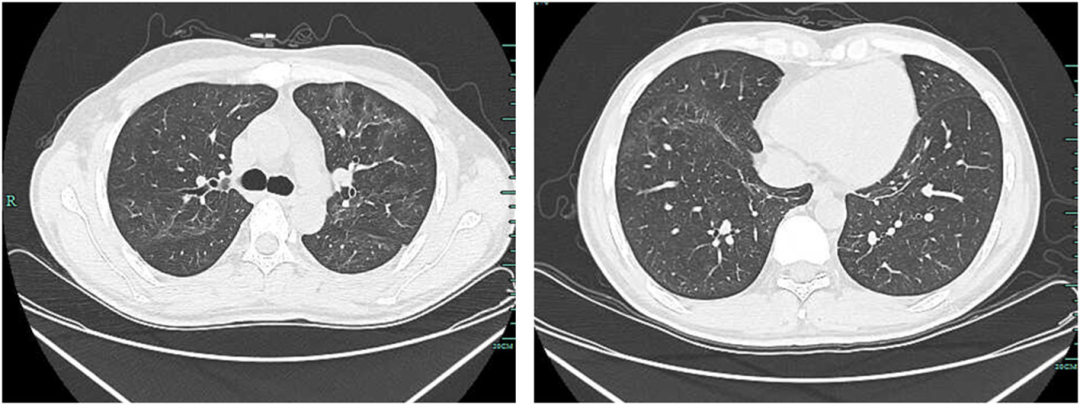

• 胸部CT显示左上肺有一个厚壁空洞,可见血管集束征和局部胸膜增厚(如图1所示)

图1:治疗前胸部CT显示左上肺厚壁空洞,内缘光滑,外缘不规则,邻近胸膜和左下胸膜增厚

接受静脉注射头孢曲松(2g,每日一次)治疗2周,口服磺胺甲恶唑-甲氧苄啶(0.96g,每日两次)。治疗一周后胸痛缓解。治疗6周后,胸部CT扫描显示肺空洞消失,只留下少量斑片状浸润。胸膜增厚情况有所改善(图2)。

图2:治疗6周后胸部CT显示空洞消失,仅留下少量斑片状浸润,胸膜增厚改善